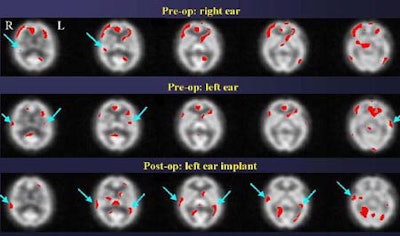

"So this implant -- in the ear that did not show dramatic pre-op activation -- nevertheless yielded a dramatic improvement in stimulation of the auditory cortex," Devous said.

However, implantation apparently failed in another subject, a 63-year-old woman who used two hearing aids preoperatively. She demonstrated fairly robust brain stimulation on both sides preoperatively, but a year after receiving a right-ear implant, showed far less stimulation, and also had some hearing loss, Devous said.

"With two hearing aids there was a synergistic effect that gave pretty good stimulation. In this case, apparently the two are not synergistic," he said. "There is some activation, so it's not that the cochlear implant isn't sending out signals; it's not that the auditory nerve isn't sending out signals; it's that whatever the brain is getting is not being recognized as speech. We're still looking at SPECT and trying to understand why poor users are poor users... I suspect we'll see this [result] again."

The final example was a resounding success.

"In this patient [below], even though the two ears appear to be equally deaf based on audiological data, SPECT data shows that the brain is getting more information from the left ear than from the right ear," and the results were validated postoperatively, Devous said.

Both subjects in which activated auditory cortices are reported preoperatively do so in the context of being unable to report having heard anything. Their auditory comprehension scores are zero after presentation of the stimuli. Thus, the rCBF response is important because it demonstrates that SPECT can predict which ear will have a better postoperative response, Devous said.

"In conclusion, we are able to use a simple SPECT imaging procedure with a fairly staightforward stimulus to map out the distribution of the rCBF response to normal speech perception, and delineate abnormalities that are associated with hearing loss," he said. "We have now 10 patients in this case series of preoperative evaluation, and in most of them we see a distinct difference between the left ear and the right ear, even though our auditory assesssments suggest they are not particularly different, and these differences may predict better outcomes in the ear providing greater stimulus to the auditory cortex."